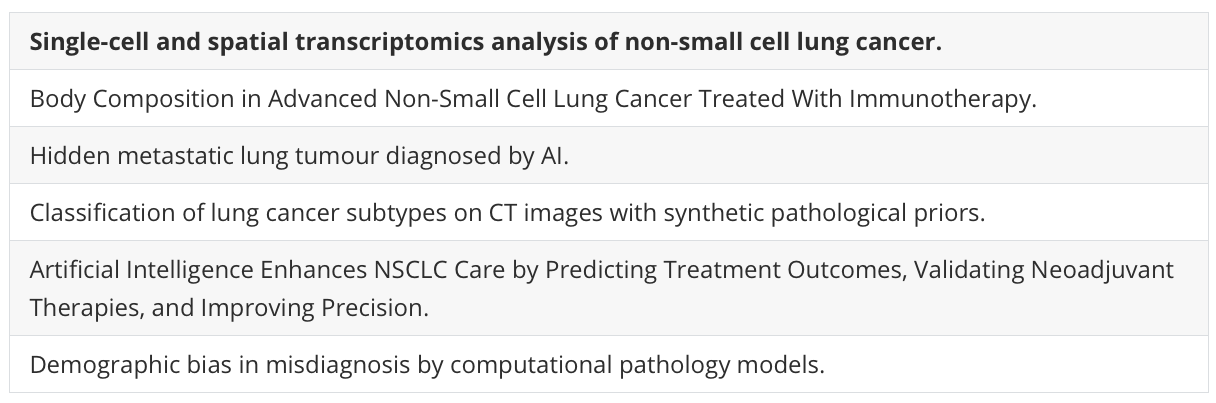

Fig. 1 展示了非小细胞肺癌(NSCLC)异质性的单细胞转录组学分析结果。

以下是对图中各个部分的分析:

A. 研究概述:从切除的肿瘤组织、邻近未受累组织(背景)以及已故捐赠者的健康肺中制备了单细胞悬浮液,并富集了CD45+或CD235-的细胞进行单细胞RNA测序(scRNA-seq)。使用新鲜冷冻的肿瘤、背景和健康组织的冷冻切片进行10x Genomics Visium空间转录组学研究。

B. 队列概览:符号代表了个体患者以及执行的分析。

C. UMAP投影:展示了肿瘤和结合背景+健康数据集的UMAP(Uniform Manifold Approximation and Projection)投影图,这是一种用于降维和数据可视化的技术。

D. 点图(Dotplot):显示了用于肿瘤样本中宽泛细胞类型注释的代表性基因。点图通常用于展示基因表达水平,点的大小代表表达量,颜色代表表达水平的变化。

E. 等高线图(Contour plot):展示了在AT2细胞(44,399个细胞)、CAMLs(2520个细胞)和AIMφ(16,120个细胞)中共表达的髓系(LYZ, CD68, MRC1)和上皮系(EPCAM)基因。这些数据被标准化、缩放和对数转换。

F. 箱线图(Boxplot):展示了在AT2细胞、CAMLs和AIMφ中髓系(LYZ, APOE, CD68, MRC1)和上皮系(EPCAM, KRT8, KRT19)基因的标准化、缩放和对数转换后的基因表达。箱形图显示了四分位数,须表示1.5倍四分位距。

G. 非免疫细胞亚群的相对比例:在CD235-富集中计算的肿瘤与背景之间的差异。箭头指示了肿瘤与背景相比的增加(↑)或减少(↓)。使用双边Wilcoxon秩和检验和Bonferroni校正进行多重比较。**P < 0.01。没有星号的箭头表示该细胞类型仅在肿瘤或背景中发现。

H. 广泛免疫细胞的相对比例:在所有免疫细胞中识别的CD235-富集中计算的肿瘤与背景之间的差异。箭头指示了肿瘤与背景相比的增加(↑)或减少(↓)。使用双边Wilcoxon秩和检验和Bonferroni校正进行多重比较。*P < 0.05, **P < 0.01, ***P < 0.001。没有星号的箭头表示该细胞类型仅在肿瘤或背景中发现。

I. 肿瘤和背景中NK、DC、B、T细胞和巨噬细胞亚群的相对比例:在CD235-富集中计算的广泛注释内的肿瘤与背景之间的差异。箭头指示了肿瘤与背景相比的增加(↑)或减少(↓)。使用双边Wilcoxon秩和检验和Bonferroni校正进行多重比较。***P < 0.001。没有星号的箭头表示该细胞类型仅在肿瘤或背景中发现。

总体而言,Fig. 1 通过单细胞转录组学和空间转录组学技术,揭示了肿瘤组织与邻近正常组织在不同细胞类型上的异质性和差异。这些结果有助于深入理解肿瘤微环境中细胞的复杂性,并为未来的治疗策略提供潜在的靶点。